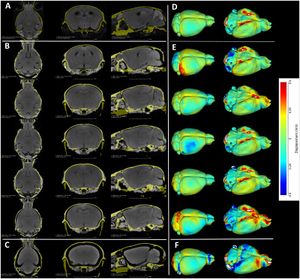

Publication: PLoS One. 2015 Dec 3;10(12):e0143821. PMID: 26633302 | PDF Authors: Gutierrez S, Descamps B, Vanhove C. Institution: Medical Image and Signal Processing Group, Ghent University-iMinds Medical IT department, Ghent, Belgium. Background/Purpose: Computed tomography (CT) is the standard imaging modality in radiation therapy treatment planning (RTP). However, magnetic resonance (MR) imaging provides superior soft tissue contrast, increasing the precision of target volume selection. We present MR-only based RTP for a rat brain on a small animal radiation research platform (SARRP) using probabilistic voxel classification with multiple MR sequences. Six rat heads were imaged, each with one CT and five MR sequences. The MR sequences were: T1-weighted, T2-weighted, zero-echo time (ZTE), and two ultra-short echo time sequences with 20 μs (UTE1) and 2 ms (UTE2) echo times. CT data were manually segmented into air, soft tissue, and bone to obtain the RTP reference. Bias field corrected MR images were automatically segmented into the same tissue classes using a fuzzy c-means segmentation algorithm with multiple images as input. Similarities between segmented CT and automatic segmented MR (ASMR) images were evaluated using Dice coefficient. Three ASMR images with high similarity index were used for further RTP. Three beam arrangements were investigated. Dose distributions were compared by analysing dose volume histograms. The highest Dice coefficients were obtained for the ZTE-UTE2 combination and for the T1-UTE1-T2 combination when ZTE was unavailable. Both combinations, along with UTE1-UTE2, often used to generate ASMR images, were used for further RTP. Using 1 beam, MR based RTP underestimated the dose to be delivered to the target (range: 1.4%-7.6%). When more complex beam configurations were used, the calculated dose using the ZTE-UTE2 combination was the most accurate, with 0.7% deviation from CT, compared to 0.8% for T1-UTE1-T2 and 1.7% for UTE1-UTE2. The presented MR-only based workflow for RTP on a SARRP enables both accurate organ delineation and dose calculations using multiple MR sequences. This method can be useful in longitudinal studies where CT's cumulative radiation dose might contribute to the total dose. |

Illustration of a CB-CT and five MR images of the same animal. a) Coronal CB-CT image and (b)-(f) biased field corrected and masked coronal MR images using a T1-weighted (b), T2-weighted (c), ZTE (d), UTE1 (e) and UTE2 (f) sequence. All CB-CT images were first co-registered using 3D Slicer version 3.6.3 by rigid body transformations using normalized mutual information. |